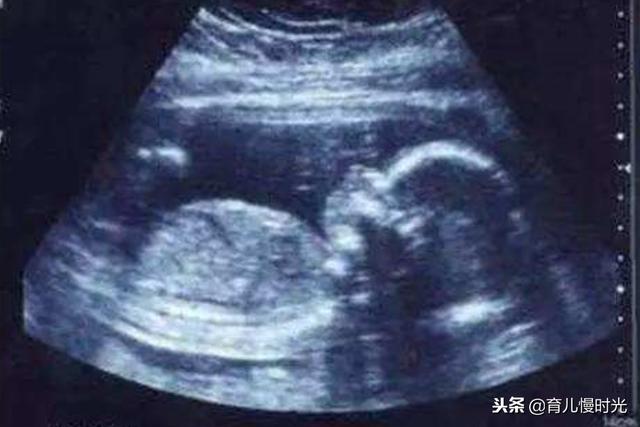

1.B超检查

通过发射和接收超声 , 将超声转化为电信号 , 最终成黑白像的过程 , 就是最基础的B超 , 探头在孕妈的肚皮上发出扇形超声波 , 所以显示器看到的范围也是扇形平面的一个黑白图 。